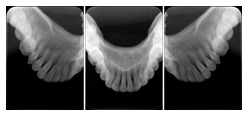

3. A patient in rural Minnesota experiences sudden vision loss and goes to a general ophthalmologist, who acquires OCT images and forwards them electronically along with a Structured Display to a retina specialist six travel hours away. The retina specialist is able to view the images in the standard layout that he is comfortable with, and to confirm that the patient has a choroidal neovascular membrane. He determines that is would be worthwhile for the patient to travel for treatment.

OCT Retinal Study with Cross Section and Navigation Structured Display

Figure OO-4. OCT Retinal Study with Cross Section and Navigation Structured Display